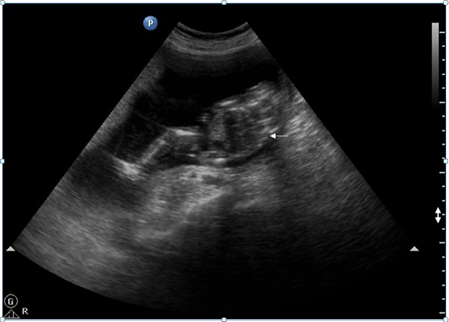

In the TRAP sequence associated with twins, the normal twin ‘pumps’ blood to the abnormal twin, called the ‘recipient’ twin, through abnormal artery-to-artery and venous-to-venous communications in the placenta. This is in conjunction with the vascular anastomosis, which takes place in TRAP syndrome.4 (Figure 2 - Figure 7).

Figure 2,3 Trans-abdominal USG shows an abnormal fetus with grossly formed lower torso and lower limbs without any discernible visceral organs and an echogenic structure casting a distal acoustic shadow, probably representing the spine of the abnormal fetus (white arrow).